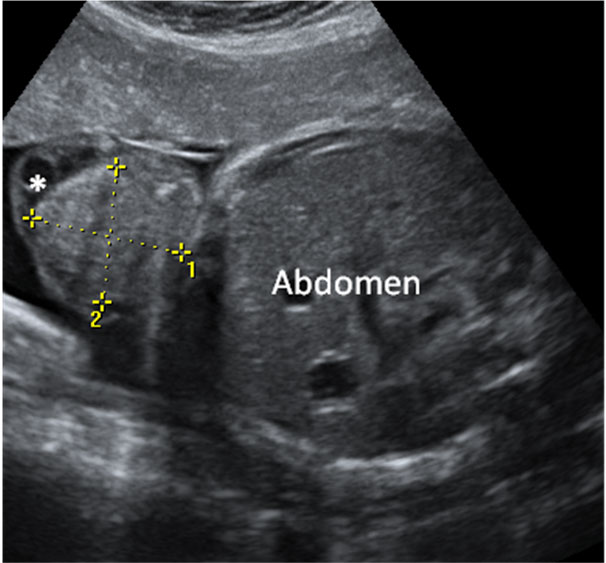

La imagen ecográfica muestra las cuatro cámaras de un corazón normal a la izquierda y de uno con canal atriventricular común (*) a la derecha.